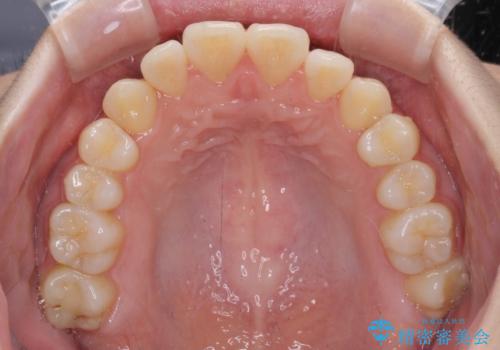

カリエール・ディスタライザーとインビザラインを用いた八重歯の改善

- 前歯の叢生と上顎左右の八重歯を気にして来院された患者様です。

奥歯の咬み合わせを見ると、左側は上顎が下顎に対して相対的に前方にあり、上下の前歯が接触していない状態でした。

咬み合わせを改善するためには、左側上顎臼歯を後方に移動させた咬み合わせにする必要があります。

インビザライン単体で改善することも可能性もありますが、インビザライン単体で達成する可能性が低いと考えられたため、カリエール・ディスタライザーという補助装置を併用して、より確実性を上げることとしました。

奥歯の咬み合わせを改善しながら、並行してインビザラインで歯列を整えることとしました。

カリエールディスタライザーを併用したことで、左側臼歯の咬み合わせを確実に改善させることができました。